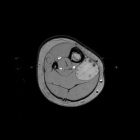

N.L. - 3 year old female with right calf mass; she denies any pain, her mother noticed it four weeks ago